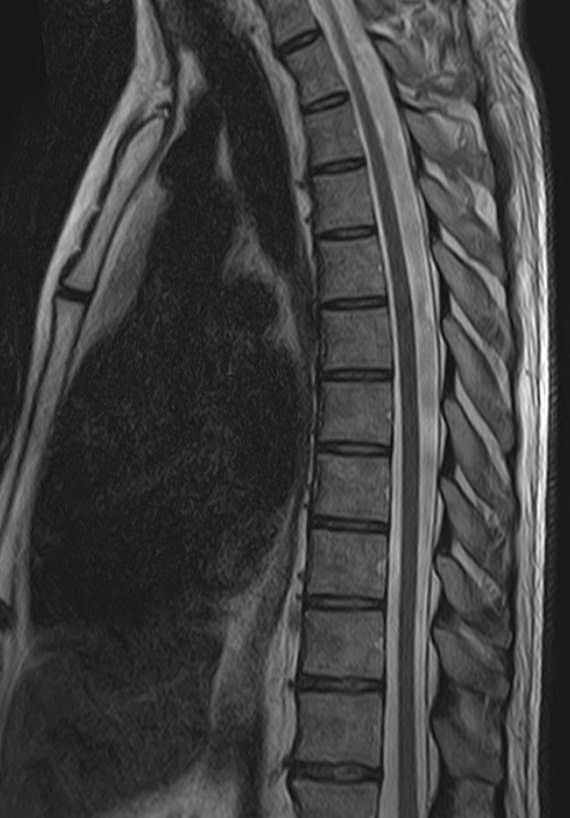

К центральной нервной системе организма относится головной мозг, расположенный в полости черепа, и спинной мозг, проходящий в спинномозговом канале позвоночного столба. В головном мозге находятся высшие центры управления всем организмом, спинной мозг имеет двусторонние связи с ними, то есть является проводником импульсов от периферии к головном мозгу и обратно.

Патология ЦНС может проявляться многообразной неврологической симптоматикой, в зависимости от уровня поражения. Причинами ее появления могут быть травматические повреждения, проникновение инфекции, демиелинизирующие и дегенеративные заболевания, сосудистая патология, опухолевые процессы.

Для диагностики заболеваний ЦНС в клинике «Доступная медицина» проводится комплексное обследование МРТ ЦНС (центральной нервной системы). Клиника укомплектована высокотехнологичным оборудованием, в частности, новейшим 32-канальным высокопольным томографом TOSHIBA VANTAGE TITAN 1,5 Тесла с высокой разрешающей способностью для точной диагностики заболеваний центральной нервной системы.

Комплексное обследование ЦНС выполняется как в стандартном режиме, когда не применяется использование контраста, так и с контрастным усилением. Для более точной диагностики некоторых патологий головного и спинного мозга внутривенно вводится контрастное вещество. С помощью контраста можно обнаружить опухолевые образования размером от 1 мм, демиелинизирующие процессы, дегенеративно-дистрофические заболевания, воспалительные процессы, сосудистую патологию.

МРТ головного и / или спинного мозга показано при диагностике повреждений, структурных отклонений или других состояний, таких как:

• грыжа, повреждение дисков позвоночника;